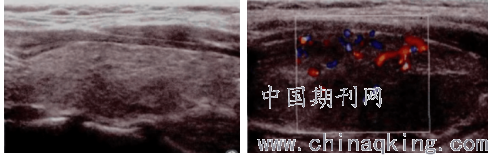

甲状腺体积轻度明显增大,两侧叶对称,部分峡部形态饱满,边界清晰,薄膜完整,网格样强回声存在一部分,且回声呈现为不同程度的减低,血流信号丰富,部分呈现为“火海征象”,如图1。

图1 实质回声和彩色血流